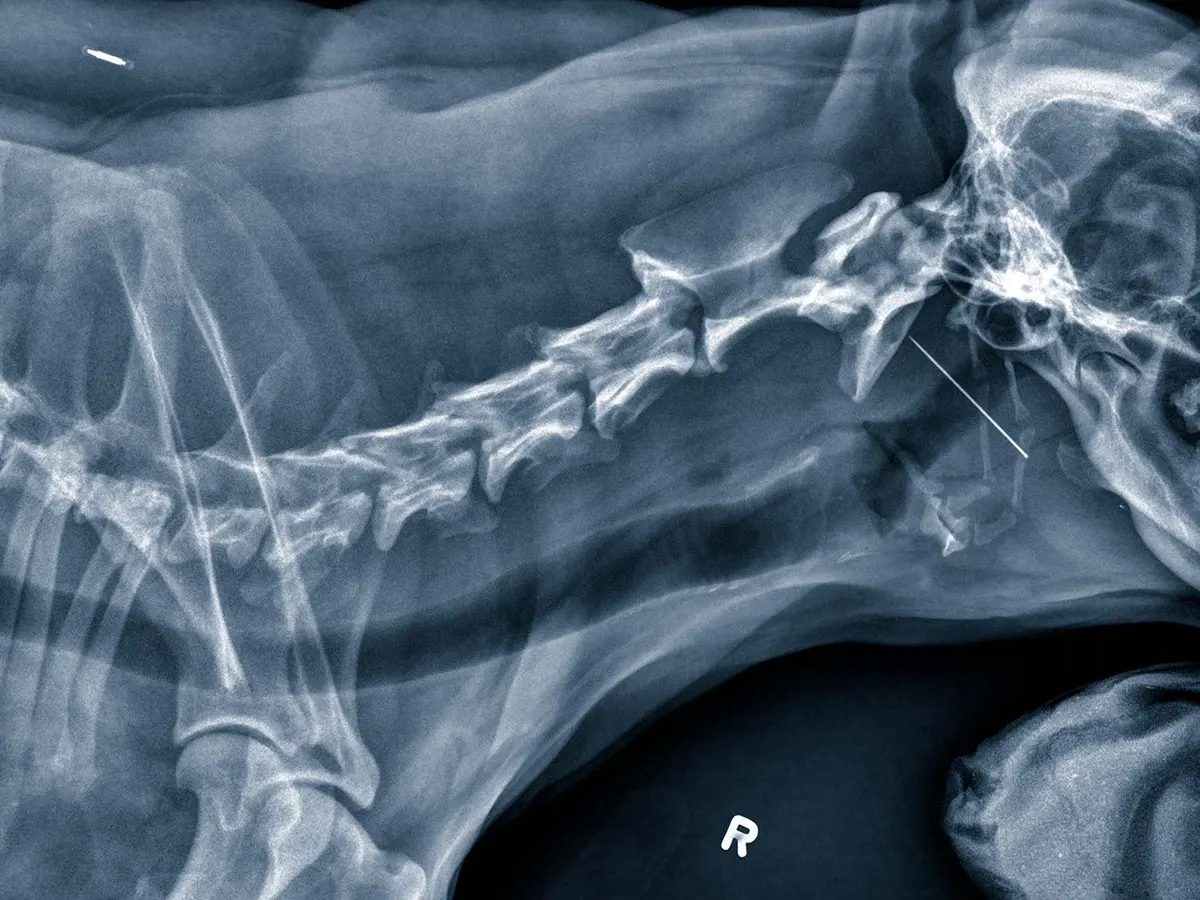

Rendgenske snimke su neinvazivan način za uvid u nutrinu naših ljubimaca.

Dvije glavne vrste tkiva u koje dobivamo uvid pomoću rendgenskog snimanja su kosti i strukture mekog tkiva.

Pomoću rendgena, između ostaloga, možemo dijagnosticirati:

Rendgenskim pregledima se također mogu pratiti zarastanja prijeloma, promatranje uspješnosti ortopedskih operacija ili rast kostiju kod mladih životinja.